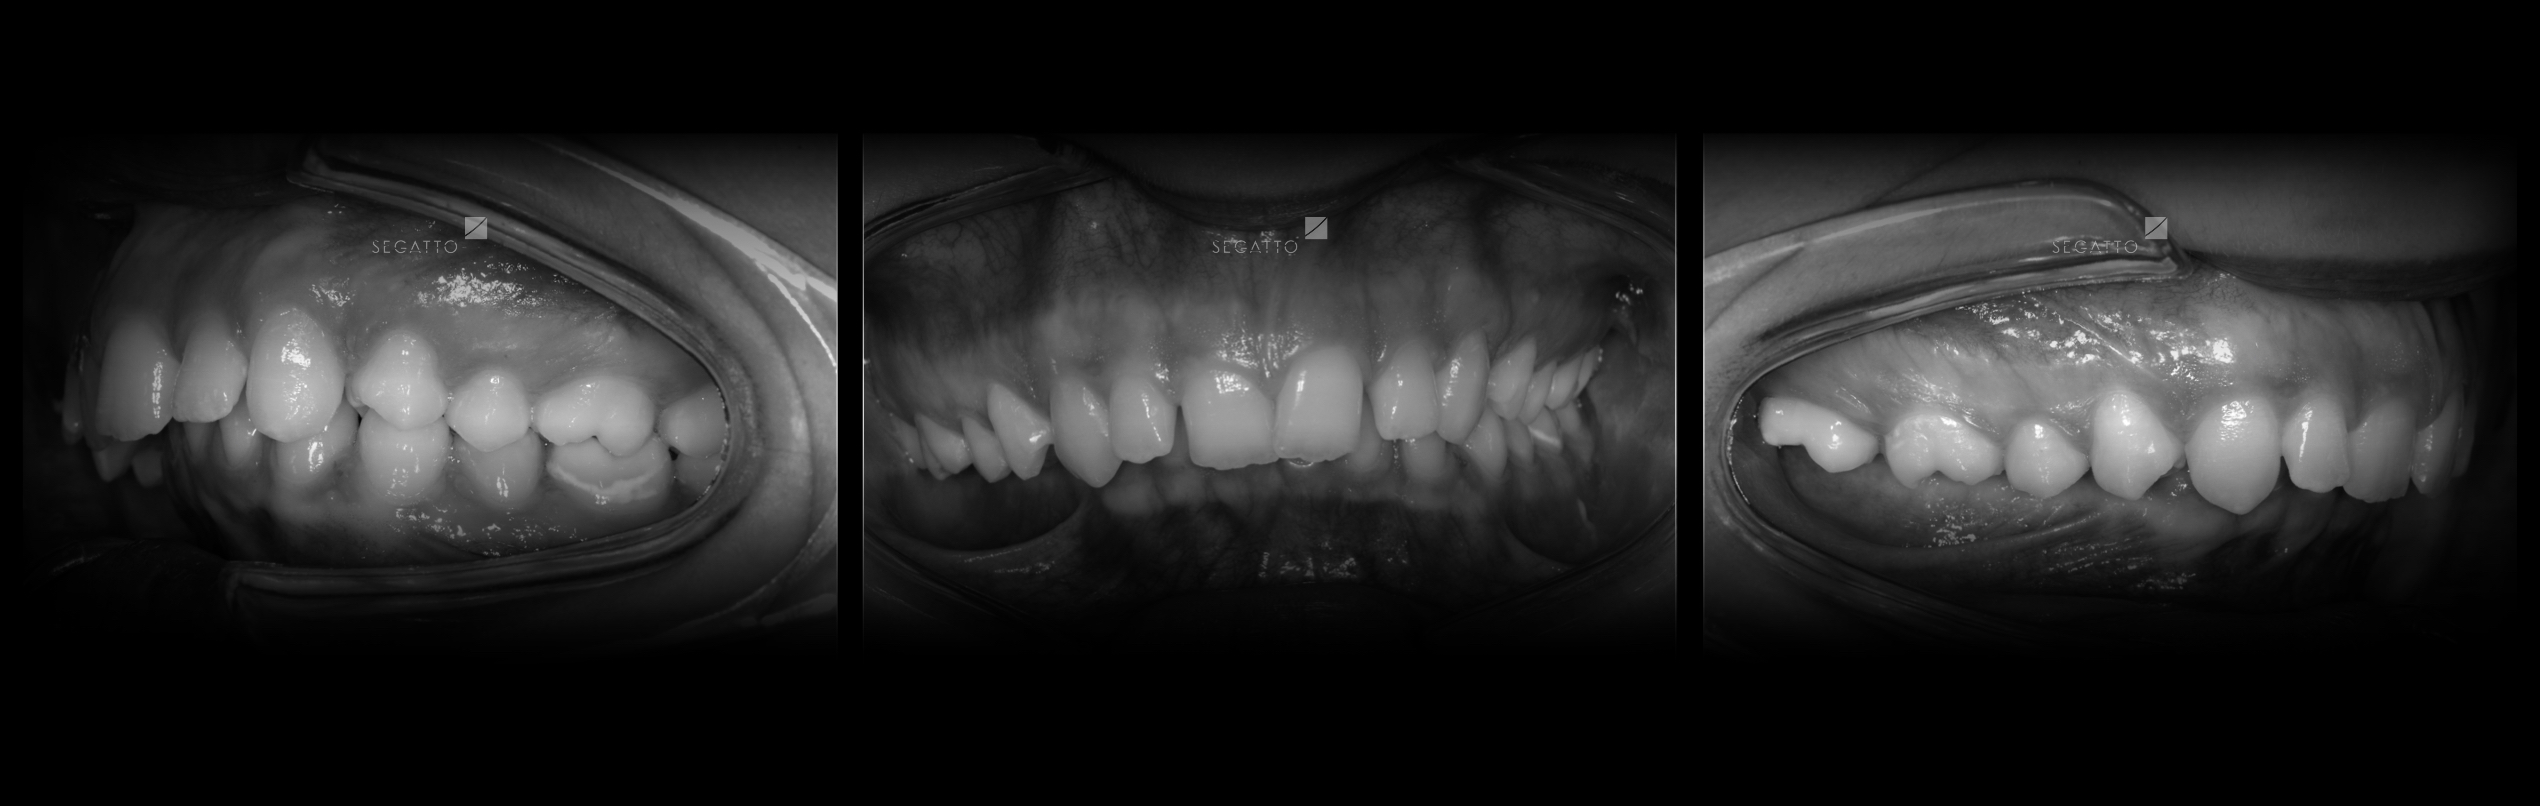

Orthodontics

Cases